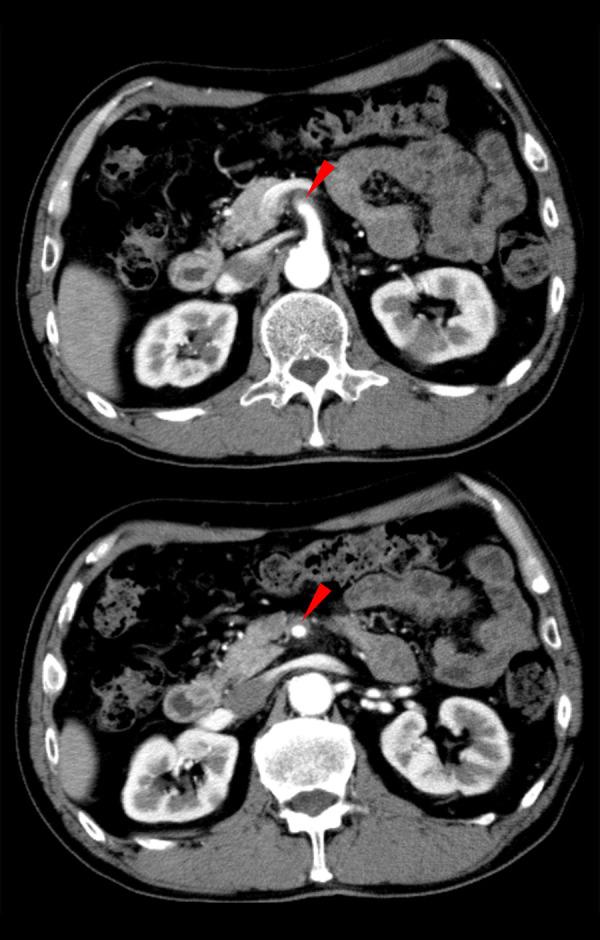

BACKGROUND Isolated superior mesenteric artery dissection (SMAD) is a rare vascular disease that is difficult to diagnose. We report a case of SMAD in a patient with an abdominal aortic aneurysm (AAA) that mimicked an impending rupture of the AAA. In addition, we describe several clinical biases that contributed to the delayed diagnosis. CASE REPORT A 66-year-old man presented with a 3-day history of abdominal pain, without a history of trauma, that worsened gradually and caused him to visit our hospital. The patient's medical history included an AAA under observation. The patient was well oriented and initially remained hemodynamically stable, and the abdomen was soft and non-tender on palpation. An emergency contrast-enhanced computed tomography (CT) scan confirmed a 44-mm AAA without any leakage, but with an isolated SMAD. His previous physician confirmed there was no change in the AAA size since 3 months prior to hospital admission. Thus, the symptoms were caused by the isolated SMAD. The patient showed improvement with pain-relieving and antihypertensive management, without anticoagulation therapy or revascularization, and was discharged on day 25 of admission without any complications. CONCLUSIONS The misdiagnosis in this case was attributable to several clinical biases, including search satisfaction, Sutton's slip, and anchoring bias. Physicians should guard against presumptive diagnoses based on patient symptoms or initial plausible findings and instead pursue a thorough workup to reach a definitive diagnosis.

背景 孤立性肠系膜上动脉夹层(SMAD)是一种罕见的血管疾病,诊断困难。我们报告一例患有腹主动脉瘤(AAA)的患者发生SMAD,其表现类似AAA即将破裂。此外,我们描述了导致诊断延迟的几种临床偏差。病例报告 一名66岁男性,有3天腹痛病史,无外伤史,疼痛逐渐加重,遂来我院就诊。患者病史包括正在观察中的AAA。患者定向力良好,最初血流动力学稳定,腹部触诊柔软无压痛。急诊增强计算机断层扫描(CT)证实有一个44毫米的AAA,无任何渗漏,但存在孤立性SMAD。其之前的医生证实自入院前3个月以来AAA大小无变化。因此,症状由孤立性SMAD引起。患者经止痛和降压治疗后病情改善,未进行抗凝治疗或血管重建,入院第25天出院,无任何并发症。结论 该病例的误诊归因于几种临床偏差,包括搜索满足感、萨顿疏忽和锚定偏差。医生应警惕基于患者症状或最初似是而非的发现进行推定诊断,而应进行全面检查以得出明确诊断。